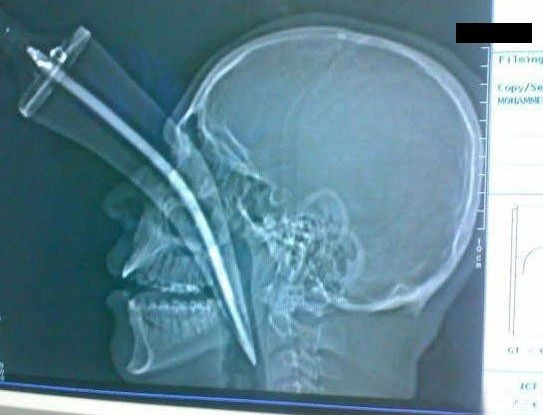

痛そうです・・・

これは痛いというレベルを超えた苦痛でしょう。

でも、この状態でも生きてられるんですね。

何が原因でこんなになっちゃたのかしら・・・